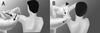

Cross body adduction test: pain w/ shoulder in 90 FF and max adduction across body

cross-body adduction test is the most sensitive provocative test for AC joint osteoarthritis at 77%, the O’Brien active compression test has been shown to be most specific at 95%. CSI injection, only 44% accurately enter the joint.